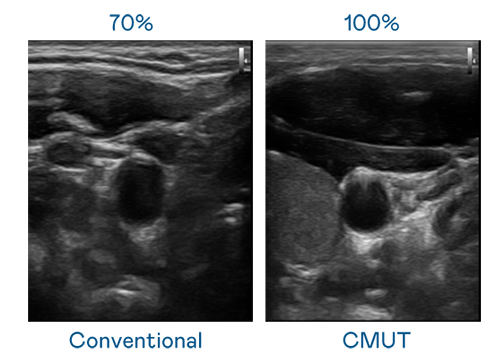

CMUT 技術是一種用電容式微機電元件來產生超音波訊號的技術。與傳統 PZT 壓電式技術相比,CMUT 頻寬增加 30%,更寬頻的超音波訊號讓影像解析度大幅提升,是實現高影像品質醫療超音波掃描、促進精準醫療發展的關鍵技術。

大頻寬帶來超清晰影像

超音波影像的解析度高低,首先取決於探頭能發出的訊號頻寬。PA视讯 CMUT 可提供高清晰的超音波訊號,提供高頻寬、高靈敏度、影像紋理細節更高的超音波影像,協助醫護人員縮短影像判讀時間及利用精準的醫療影像進行診斷。